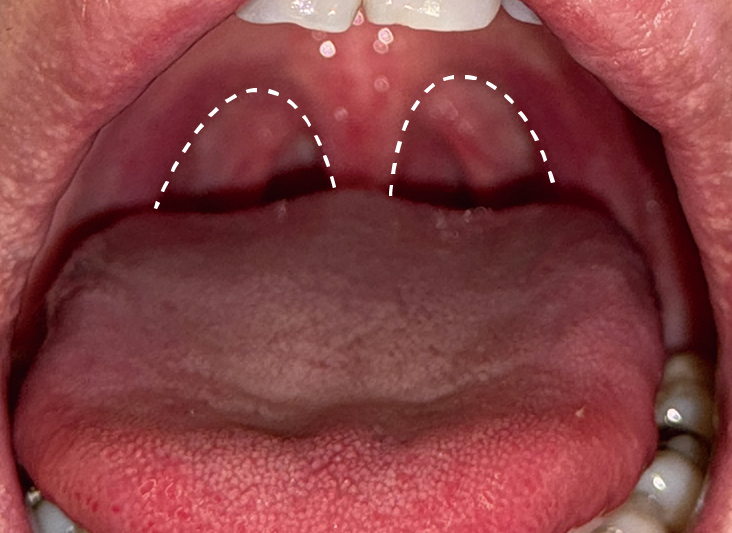

いびきレーザー治療の症例写真

After(1回目)

After(2回目)